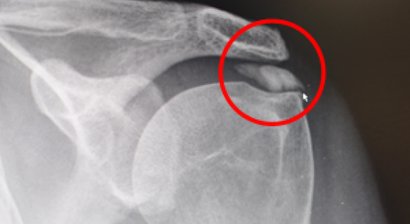

Schulterluxation

Das Schultergelenk ist das am wenigsten stabile Gelenk unseres Körpers. Dadurch haben wir einerseits die Möglichkeit, den Arm in alle Richtungen zu bewegen. Andererseits ist die Schulter deshalb auch am häufigsten von Verrenkungen betroffen. Bei einer Schulterverrenkung (lateinisch: L...